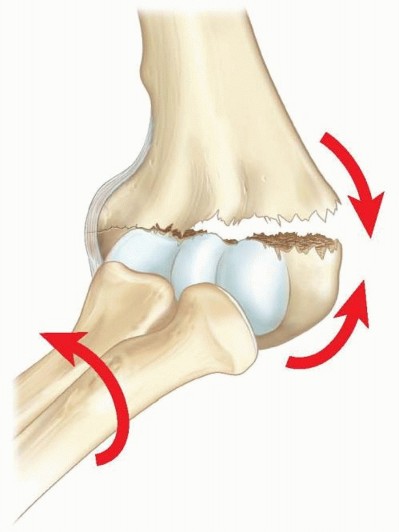

11 MIN READ Open Reduction and Internal Fixation of Fractures of the Medial Epicondyle يناير 2023 Read More